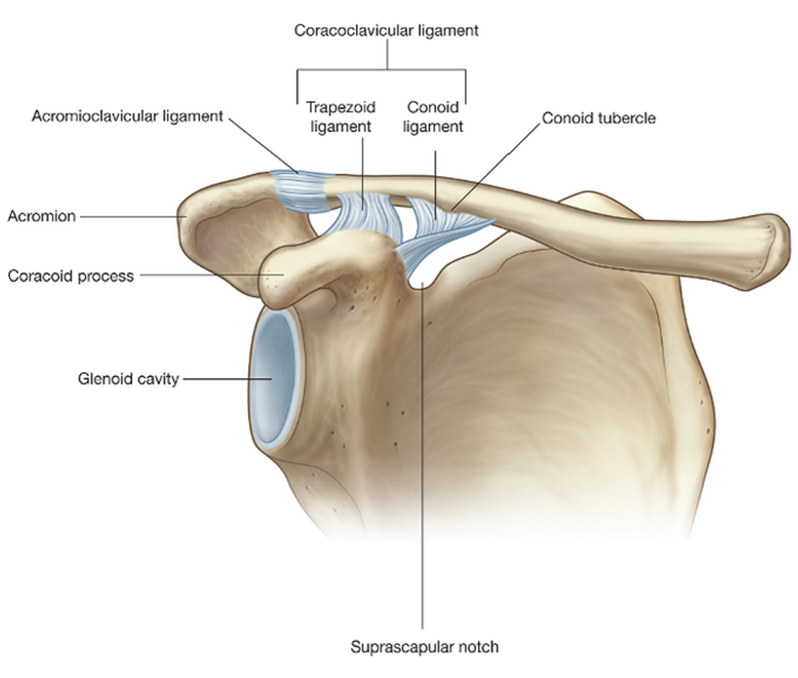

Review this diagram of the scapula

Diagram of the lateral view of the scapula